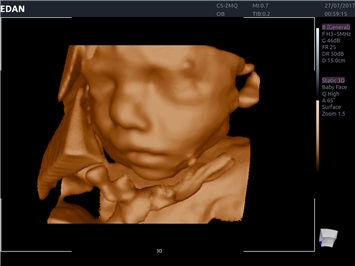

EDAN Acclarix LX4

Расширьте свои представления. Использование усовершенствованной платформой Acclarix система LX4 обеспечивает непревзойденную четкость изображений и интеллектуальный рабочий процесс для всех пользователей, являясь при этом наиболее экономичным решением.

EDAN Acclarix LX4 представляет собой инновационную ультразвуковую систему, построенную на усовершенствованной платформе Acclarix. Сочетание высокого качества визуализации с интеллектуальным рабочим процессом делает эту систему оптимальным выбором для клиник, ценящих эффективность и экономичность.

• 3D/4D-визуализация с автоматическим редактированием объема (eFace)

• Автоматизированные измерения в акушерстве

• Акушерства и гинекологии